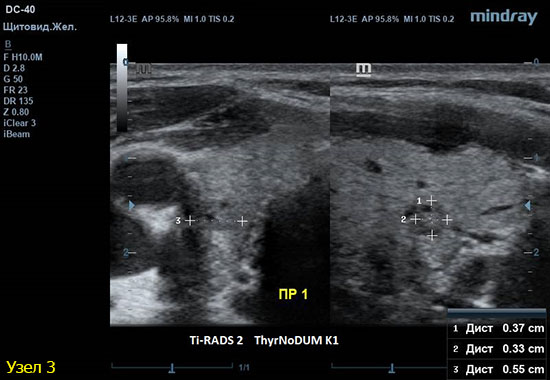

3) Узел правой доли, не прорастает капсулу щитовидной железы (0 баллов), больше широкий чем высокий (0 баллов), не имеет кальцинатов (0 баллов), с ровным четким контуром (0 баллов), изоэхогенный (1 балл), смешанной структуры (1 балл). Количество баллов 2, ACRTi-RADS2, ThyrNoDUMК1. Пункция не показана в связи с низким риском.